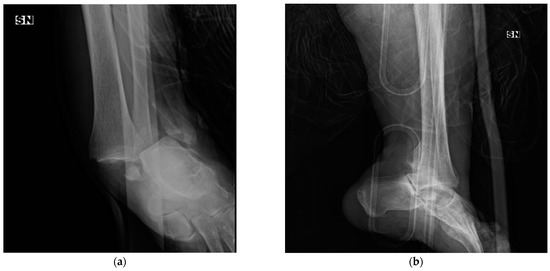

In 1947, David M. Bosworth [1] reported five cases of particular fracture-dislocation of the ankle, in which the proximal fragment of the fibula was incarcerated behind the posterior tibial tubercle. Since that time, this rare ankle fracture pattern has been called “Bosworth fracture” (an example is shown in Figure 2).

Figure 2.

X-ray of a Bosworth fracture (a) anterio–posterior (AP) pre-operative view, (b) lateral pre-operative view, (c,d) post-operative X-rays, and (e,f) the 4-month follow-up.